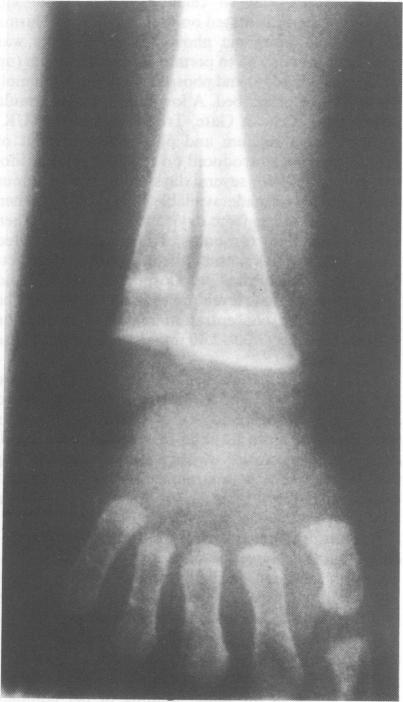

Two separate episodes of rickets developed in a female infant of 25 weeks gestation and birthweight 690 g, who had congenital hypothyroidism and required parenteral nutrition for more than 100 days. We speculate that there is a relationship between metabolic bone disease of prematurity and the preterm infant's thyroid status.

一名孕25周、出生体重690克的女婴出现了两期独立的佝偻病,该女婴患有先天性甲状腺功能减退症,需要肠外营养超过100天。我们推测早产代谢性骨病与早产儿的甲状腺状况之间存在关联。